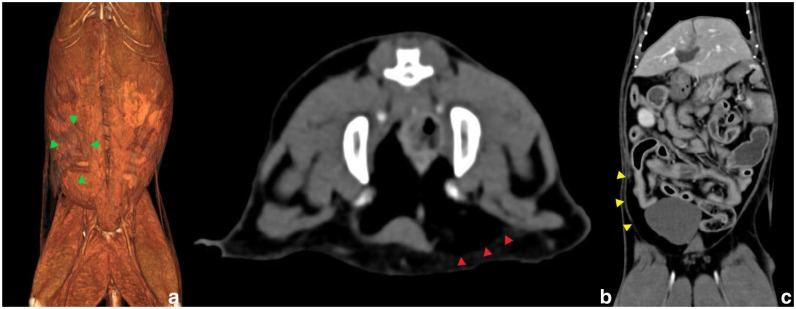

Case summary: A 16-year-old female spayed domestic shorthair cat presented with an acute mass-like outpouching of abdominal viscera unilaterally in the right caudal abdominal ventrum without history of trauma. This abnormality was not identified on prior diagnostic investigations for hyporexia up to 3 weeks prior. A CT examination revealed a protrusion of the viscus through an area of anomalous abdominal wall thinning associated with the discontinuation of the transverse abdominis muscle in this region, rather than a true hernia. Exploratory celiotomy confirmed these findings, with the external rectus sheath and parietal peritoneum remaining intact without an overt hernia ring identified. Abdominal wall augmentation and reconstruction using internal abdominal oblique advancement and fold-over external rectus sheath imbrication resulted in complete resolution without recurrence on subsequent follow-ups. Despite gastrointestinal and muscle biopsies showing no evidence of neoplasia on histopathology, the patient developed an abdominal effusion and was diagnosed with granular lymphocyte lymphoma 4 weeks postoperatively, leading to euthanasia.

Relevance and novel information: This case describes a non-traumatic abdominal wall pseudohernia in a geriatric cat, a condition which has not previously been reported. A novel reconstruction technique was used to correct the body wall anomaly, with a good short-term outcome without recurrence.